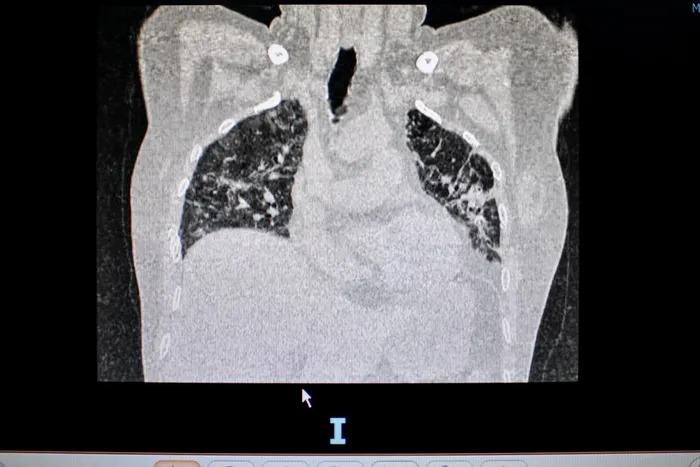

Trên phim chụp phổi cắt lớp vi tính, các bác sĩ phát hiện người đàn ông bị tổn thương phổi dạng xơ hóa, giãn phế quản. Đây là di chứng vĩnh viễn, dù điều trị nhưng khó trở về bình thường.

Mới đây nhất, một phụ nữ 52 tuổi đến khám trong tình trạng suy hô hấp mạn tính, phải mang theo bình oxy dù khỏi Covid-19 gần một tháng. Trên phim X-quang, hai bên phổi của bệnh nhân mờ đục, diện tích tổn thương nhiều.